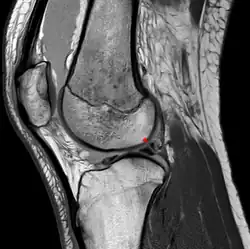

In der MRT muss der Verlauf der Ligamenta meniscofemoralia berücksichtigt werden, um eine Verwechslung mit einem verlagerten Anteil des Außenmeniskus bei einem Riss desselben zu vermeiden.[10]

Das Ligamentum meniscofemorale (Meniskus-Oberschenkelknochen-Band) ist eine Bandstruktur, die vom Hinterhorn des Außenmeniskus zum innenseitigen Femurkondylus verläuft. Zwar werden auch Bänder vom Vorderhorn des Meniskus und solche vom medialen Meniskus beschrieben, ihre Häufigkeit scheint jedoch deutlich geringer zu sein.[1]

- das Ligamentum meniscofemorale posterius (auch Ligamentum Wrisberg) hinter dem hinteren Kreuzband und

- das Ligamentum meniscofemorale anterius (auch Ligamentum Humphry) vor dem hinteren Kreuzband verlaufend.[2][3][4]